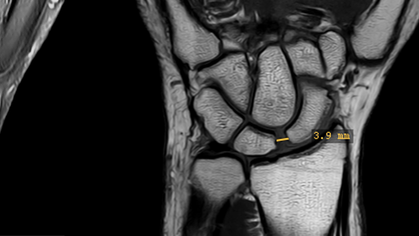

Im Jahre 2001 übernahm er in der Suva die Chefarztfunktion. Er restrukturierte die Abteilung Versicherungsmedizin und etablierte eine ärztliche Führungsstruktur, um die fachliche Unabhängigkeit der ärztlichen Expertinnen und Experten zu stärken. Unter seiner Leitung führte die Suva im Jahre 2005 ein Röntgenbildmanagementsystem (PACS/EBIDA) ein, mittels welchem sich Bilder zwischen Spitälern, Instituten und der Suva elektronisch austauschen lassen. Um die Qualität auch der von der Suva extern beschafften Gutachten zu sichern, entwickelte er mit seinen Mitarbeitenden einen speziellen Gutachtenclearing-Prozess, welcher 2013 durch die Internationale Vereinigung für Soziale Sicherheit ausgezeichnet wurde. Die Suva-Forschungsförderung wurde neu positioniert und Suva Medical zu einer Web-Publikation weiterentwickelt.